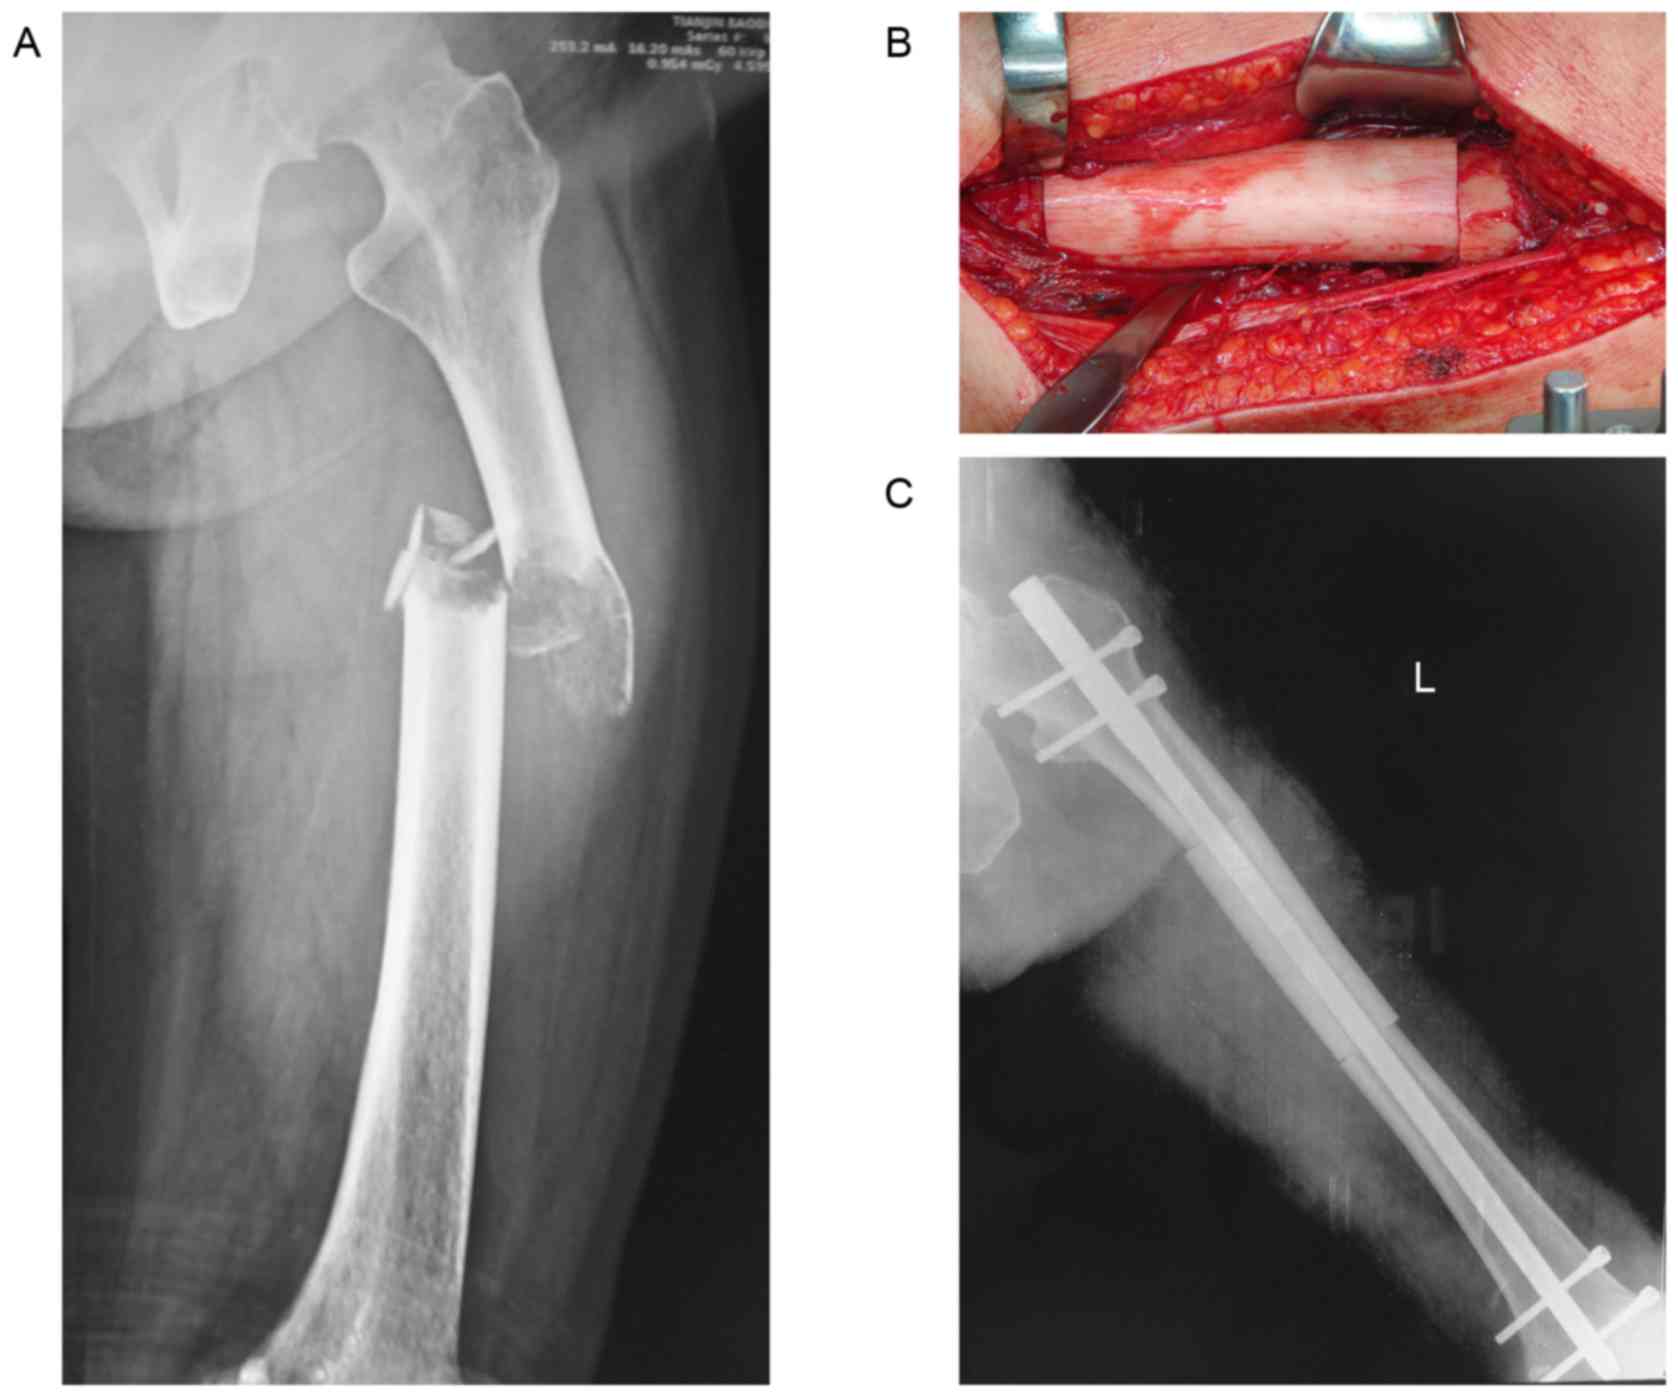

View Femur Bone Cancer Surgery Pictures. During an open reduction, orthopedic surgeons reposition your bone pieces during surgery, so that they are back in their proper alignment. Bone cancer destroys normal bone tissue.

A bone tumor is a neoplastic growth of tissue in bone. Your doctor removes the part of the bone with cancer but not nearby muscles, tendons, or other tissues. Outcome of skeletal reconstructive surgery for metastatic bone tumours in the femur.

The shaft is relatively wide at the proximal end but becomes. It's localized to just the femur bone, but the cancer also 'ate' away and deteriorated it to the. Cigarette smoking is associated with poor healing and increased complications after bone surgery. A bone tumor is a neoplastic growth of tissue in bone.